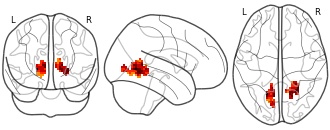

"name": "Multi_VBMgreater_fMRIenhanced",

"description": "Multi-modal analysis in BPD. Brain regions exhibiting greater gray matter and enhanced activation during emotion processing in BPD compared to healthy controls. Note: Results were thresholded at p<.0025. Note2: Results were updated (see Erratum for this publication).",